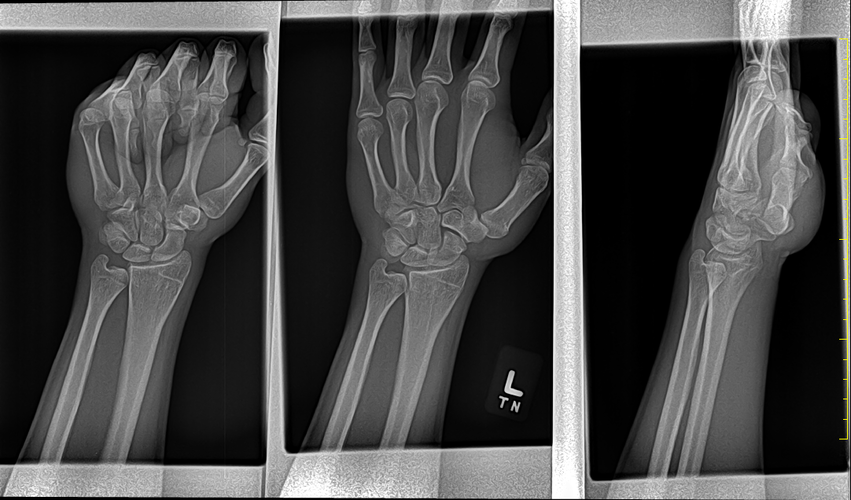

This is my last post regarding growth plates. I took xrays today.

apparently my growth plates are almost fully closed. Some of you say their done but,

these AI's told me my bone age looks like 18 and 13. YES THIS BONE AGE AI WEBSITE SAID MY BIOLOGICAL AGE LOOKS 13 ACCORDING TO THE XRAY.

apparently my growth plates are almost fully closed. Some of you say their done but,

these AI's told me my bone age looks like 18 and 13. YES THIS BONE AGE AI WEBSITE SAID MY BIOLOGICAL AGE LOOKS 13 ACCORDING TO THE XRAY.